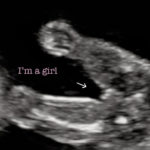

Ultrasound for Gender (15 weeks & up}